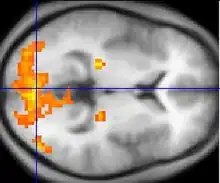

Une coupe d'une IRM fonctionnelle du cerveau. Cliquer ici pour une animation allant du haut de la tête vers le bas.

La méthode la plus utilisée actuellement est celle basée sur l'aimantation de l'hémoglobine contenue dans les globules rouges du sang. L'hémoglobine se trouve sous deux formes :

• les globules rouges oxygénés par les poumons contiennent de l'oxyhémoglobine (molécule non active en RMN) ;

• les globules rouges désoxygénés par le métabolisme des tissus contiennent de la désoxyhémoglobine (active en RMN car fortement paramagnétique).

En suivant la perturbation du signal de RMN émis par cette molécule, il est donc possible d'observer l'afflux de sang oxygéné, qui chasse le sang désoxygéné. Lorsqu'une zone du cerveau augmente son activité, un afflux de sang oxygéné lui parvient grâce à un mécanisme combinant la dilatation des vaisseaux sanguins à divers autres mécanismes mal élucidés, ce qui répond ainsi à la demande de consommation locale en dioxygène des cellules actives : c'est le signal BOLD. En faisant l'acquisition d'images pondérées T2* à une cadence rapide (environ une image toutes les secondes, voire moins), il est possible de suivre en direct, sous forme de film, les modulations de débit sanguin liées à l'activité cérébrale, par exemple lors d'une tâche cognitive.